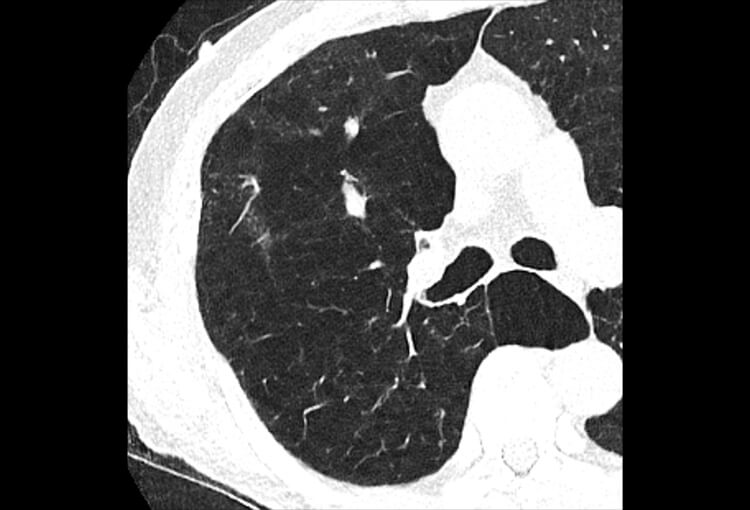

120 kV / 20 mAs / 1 mm

Before FBP (Noise 189) VS After ClariCT.AI (Noise 46) 76% Denoising